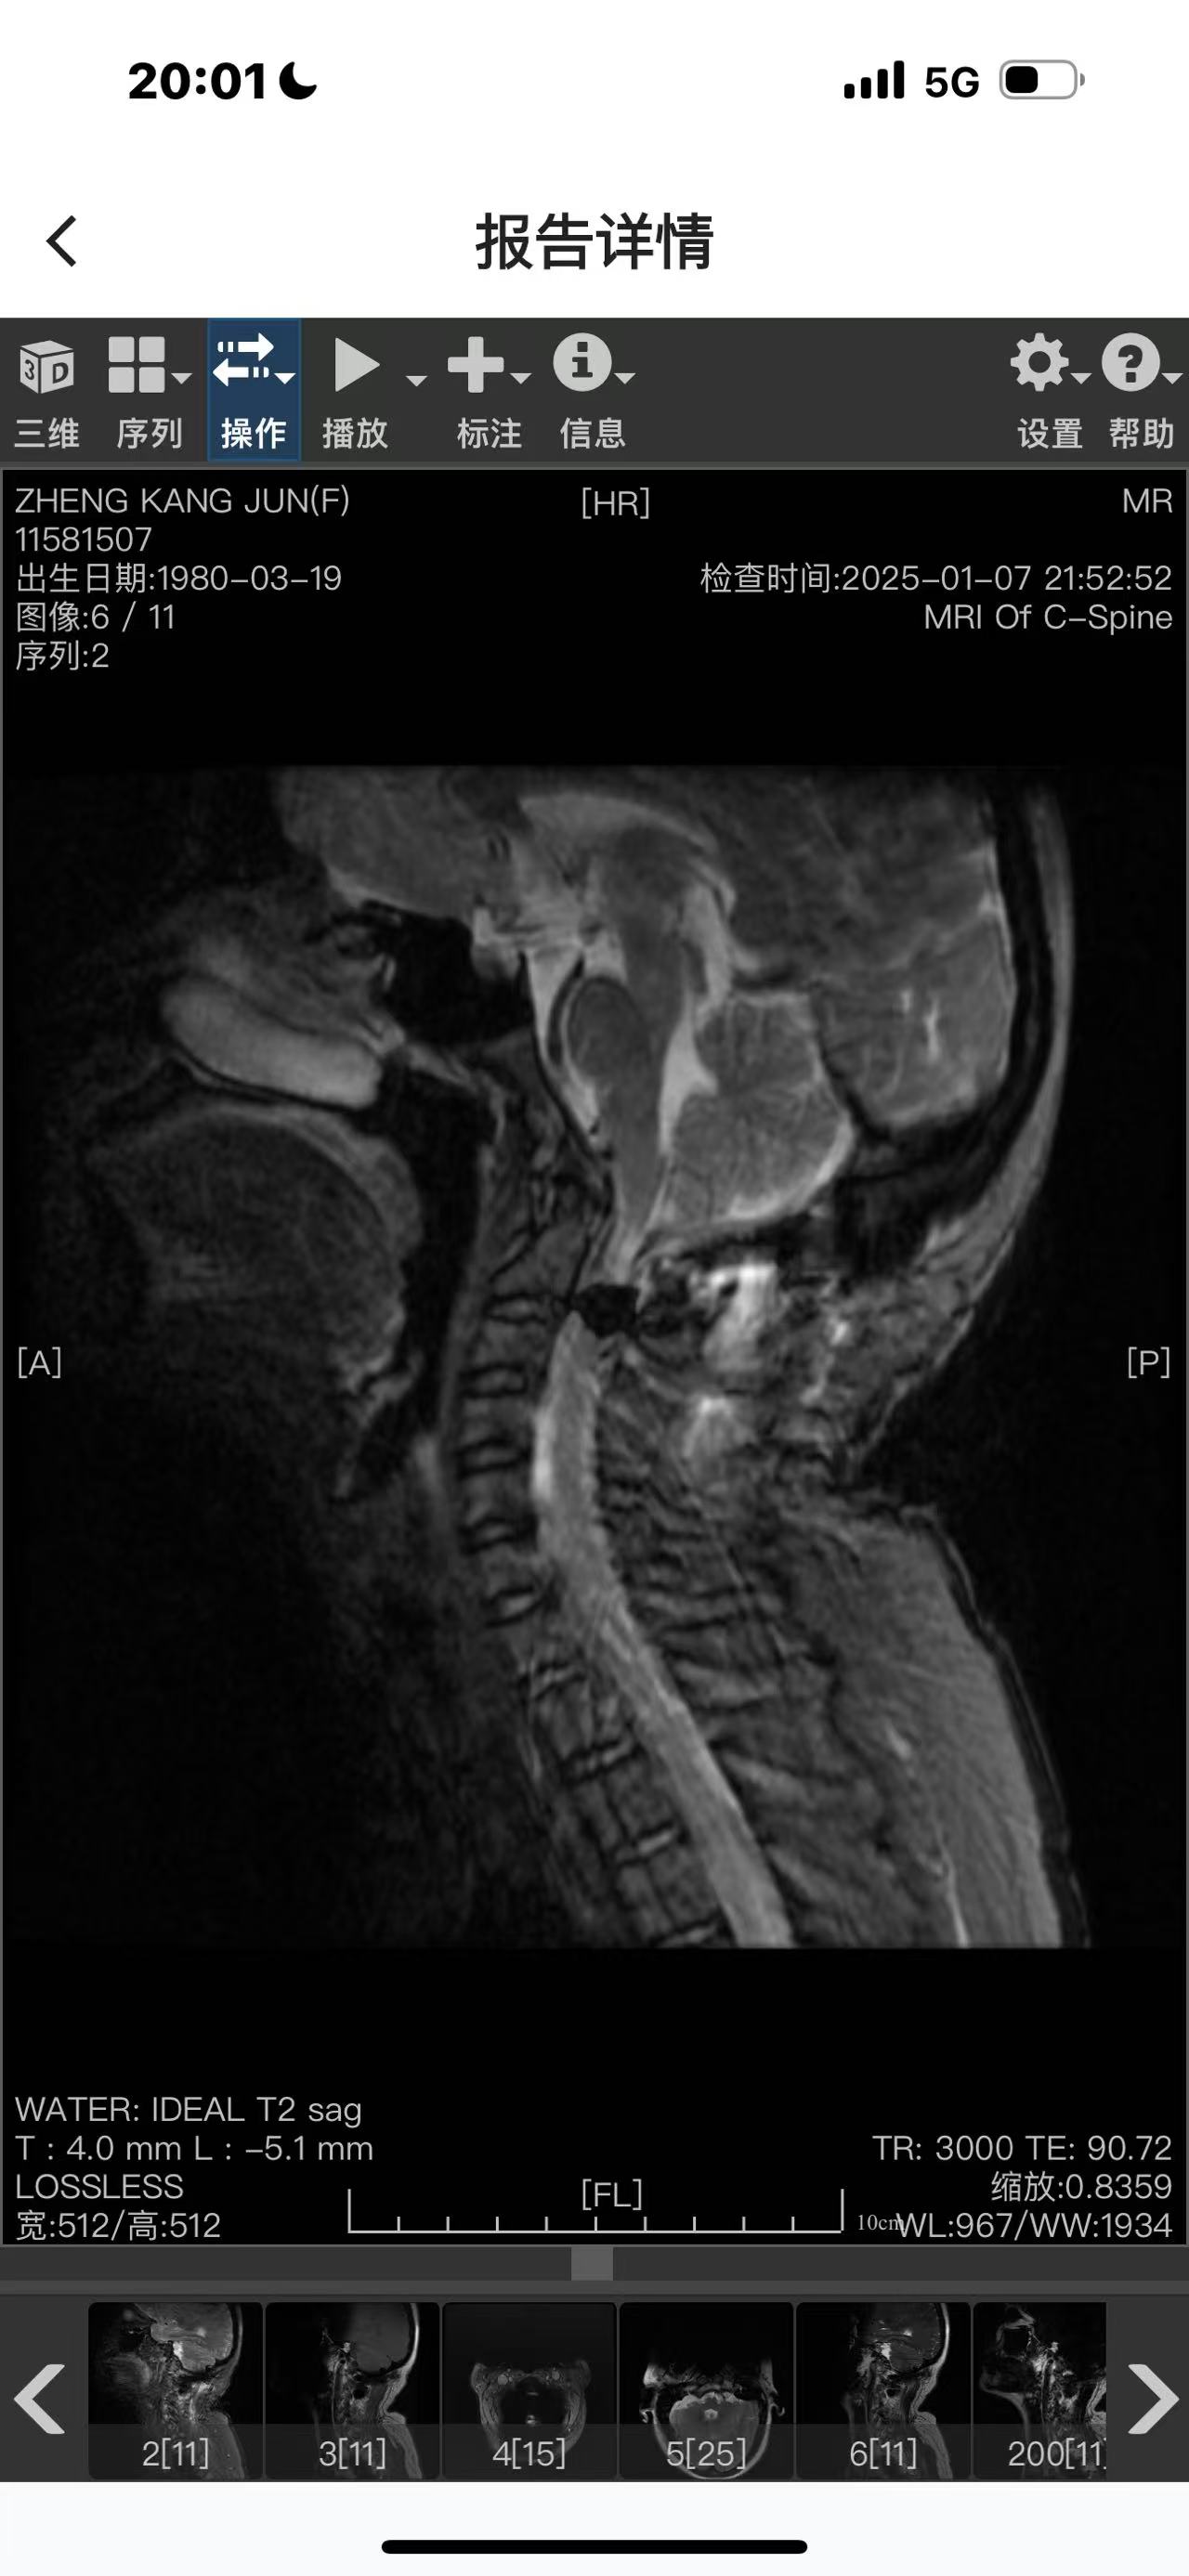

• 诊断:寰枢椎脱位

• 影像: